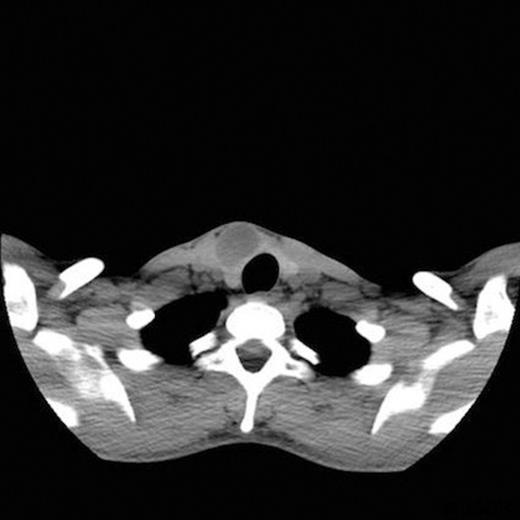

A 25-year-old man presented to the otolaryngology department with a one-year history of a asymptomatic, anterior triangle neck swelling which he had incidentally noticed. On examination, there was a 3×2cm swelling just right of the midline which moved with swallowing. There was no neck lympadenopathy. The remainder of ENT examination was unremarkable with nasendoscopy showing normal cord movements. Biochemically, he was euthyroid. The general practitioner had organised an ultrasound that showed a 33×26x19mm complex cyst in the right lobe of the thyroid gland. A fine needle aspiration (FNA) was performed and a non-contrast CT scan was requested. The FNA was reported as Thy1; a subsequent ultrasound guided FNA also was reported as Thy1. The CT scan showed a cystic lesion (figure 1) which seemed to be arising from the right lobe of the thyroid gland. Treatment options were discussed and he was listed for a diagnostic right hemithyroidectomy.

In our case, preoperative imaging has suggested thyroid pathology therefore the intra-operative findings were unexpected. The preoperative CT did not have contrast enhancement as thyroid malignancy was a differential diagnosis. The blood filled cavity of the lesion was presumably due to the previous FNAs. The position of the schwannoma between the strap muscles was consistent of the nerve of origin being a branch of the ansa cervicalis.